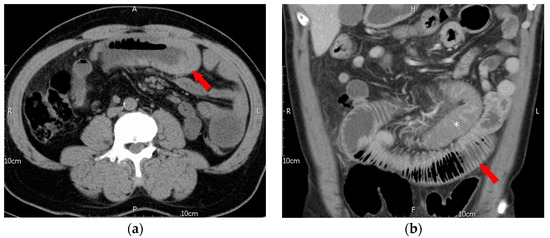

5.4. Image Findings